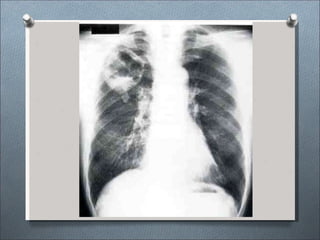

Formas clínicas radiológicas:

•Enfermedad asintomática y tipo gripal.

•Tipo neumónico: Consolidación parenquimal de

lóbulos inferiores.

•Ensanchamiento linfático hiliar o mediastinico.

•Neumotórax.

•Lesiones nodulares con o sin cavitación.

•Lesiones miliares.